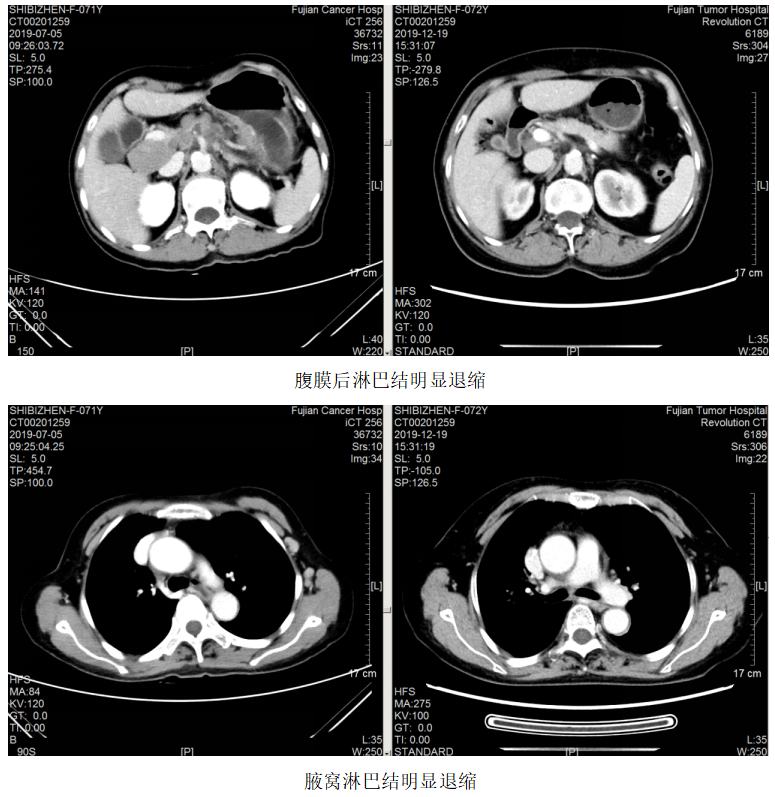

胸部CT:1、左锁骨区、左腋窝多发肿大淋巴结,考虑转移,建议随访,全腹CT:考虑食管胃交界癌累及胃周脂肪并腹腔腹膜后淋巴结多发转移(CT分期约T4aN3)。

图1.2019.7.5影像(基线评估)

一线治疗:2019.7.12~10.24予FOLFOX方案(奥沙利铂110mg+左亚叶酸钙300mg+5-Fu 2.75)化疗8周期,曲妥珠单抗220mg靶向治疗7次。

疗效评估:PR。

维持治疗:2019.11.6~2022.03.02予方案“卡培他滨+曲妥珠单抗q3w”维持治疗。